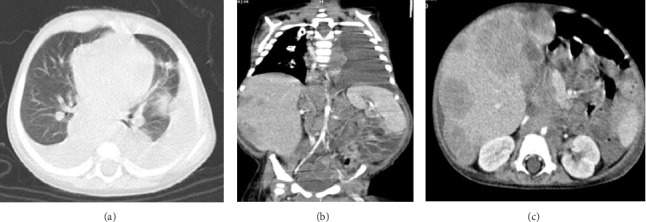

Infantile hepatic hemangioma (IHH) is rare, but the most common benign hepatic tumor in the first year of life. It has a characteristic course with perinatal presentation, increasing growth during the first year of life, and subsequent shrinkage of the vascular lesions. The authors report a 12-month-old male infant who presented with severe abdominal distension and respiratory distress while under workup for diffuse IHH since 2 months of age. In addition, the child's situation was complicated by two uncommon occurrences: bilateral chylothorax and the presence of neuroblasts and rosette cells in the pleural fluid. The detection of such cells in pleural fluid is extremely rare in pediatric neuroblastoma cases. This complex medical scenario highlights the challenges faced in diagnosing and managing rare pediatric conditions, emphasizing the need for careful monitoring and comprehensive diagnostic approaches in similar cases.

Abstract Image